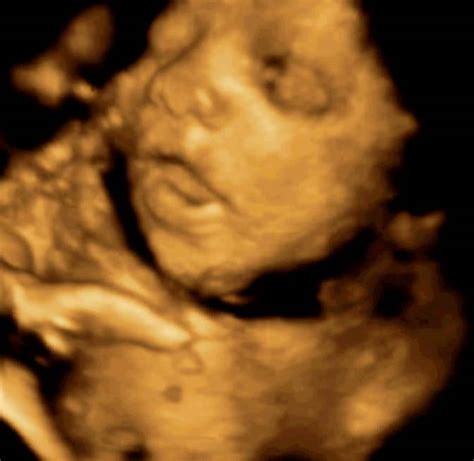

Učinki kajenja na vašega otroka